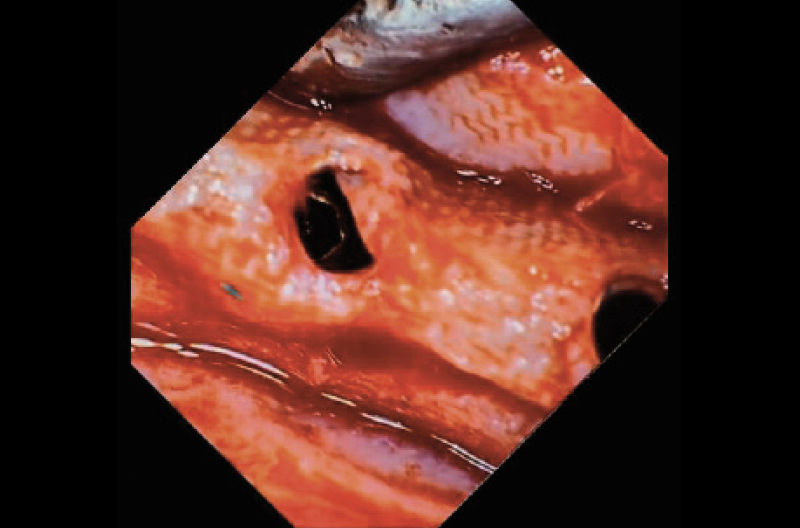

Preparati i siti con le frese di osseodensificazione dedicate, sono stati inseriti 4 impianti Leone Narrow XCN® 2.9 secondo le modalità sopra descritte. Solo per ridurre al minimo il rischio di riassorbimento osseo, soprattutto in cresta, zona maggiormente stressata nelle fasi di osseodensificazione ed espansione con le frese, ho preferito proteggere il sito chirurgico attraverso un minimo riempimento con biomateriali eterologhi e una membrana riassorbibile fissata attraverso chiodini di osteosintesi (Figg. 5 a, b).

Figg. 5 a, b – Radiografia endorale effettuata alla fine dell’intervento che evidenzia la posizione degli impianti Leone XCN® 2.9 e la presenza dei chiodini di stabilizzazione della membrana riassorbibile

Figg. 7 a-e – Fotografie endorali effettuate al momento della riapertura degli impianti Leone XCN® 2.9, trascorsi 5 mesi dall’intervento, che evidenziano la completa osteointegrazione degli impianti completamente sommersi e senza alcuna esposizione

Fig. 7 b

Fig. 7 c

Fig. 7 d

Fig. 7 e